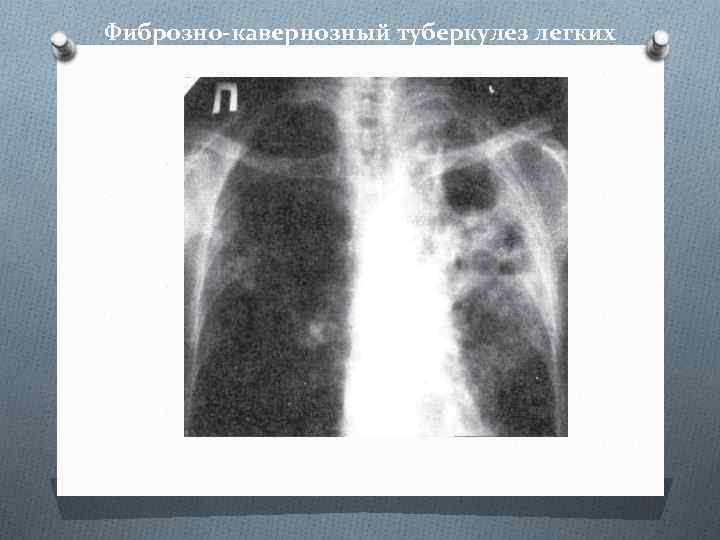

Понимание кавернозного туберкулеза почки

Раздел: Мудрость в деталях